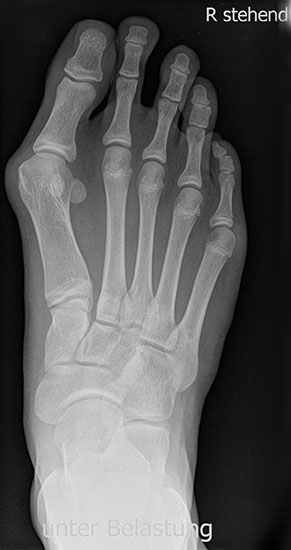

Röntgen

Standard ist die belastete Röntgenaufnahme des Fußes dorso-plantar und seitlich. Günstig ist eine Röhrenkippung von 10°-20°, um die Gelenke der Lisfranc-Linie einsehen zu können.

• Hallux valgus Winkel

• Hallux valgus interphalangeus Winkel

• Intermetatarsalwinkel I zu II

• Distaler Metatarsale Gelenkwinkel (PASA)

• Form des Mittelfußknochenkopfes

• Winkel Metatarsale I Basis zum Os cuneiforme mediale

• Metatarsalindex

• Elevation/ Plantarisierung I. Strahl

• Pes metatarsus adductus

• Wachstumsfugen